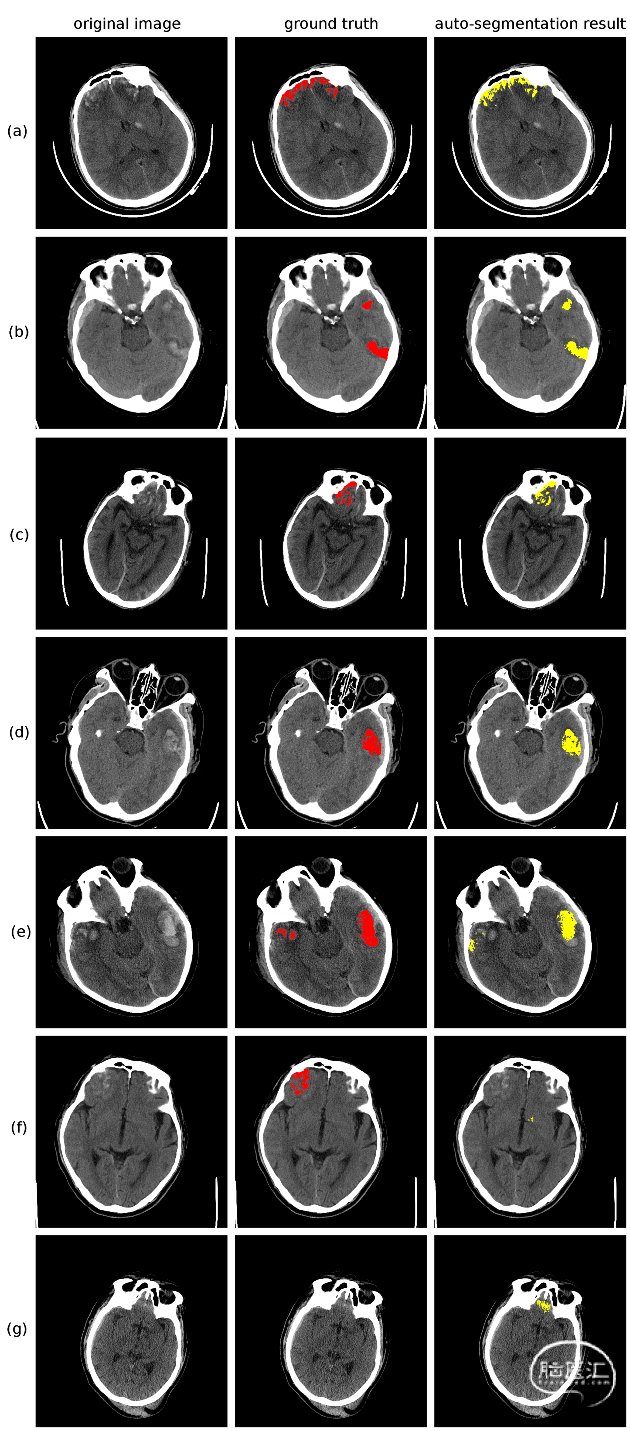

1. Attention-3DUNet神经网络可以有效地分割脑挫裂伤性血肿区域

经过训练,Attention-3DUNet神经网络在测试集上实现了0.82±0.30的Dice值,综合表现由于其他3D-UNet和VNet神经网络模型。其能够对大部分脑挫裂伤性出血区域进行分割,然而由于脑挫裂伤出血的高度不规则性和弥散性,部分血肿区域分割不准确,还需要医师进行人为核对。